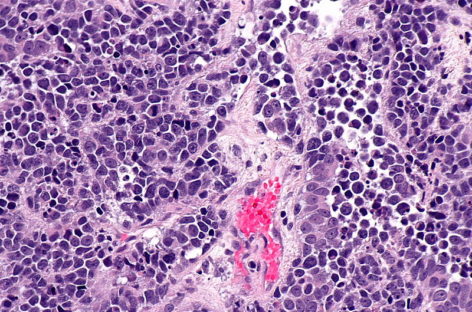

Hemoleucograma esenţială în depistarea cancerelor de sânge. Ar trebui să devină o rutină anuală 15 feb 2021